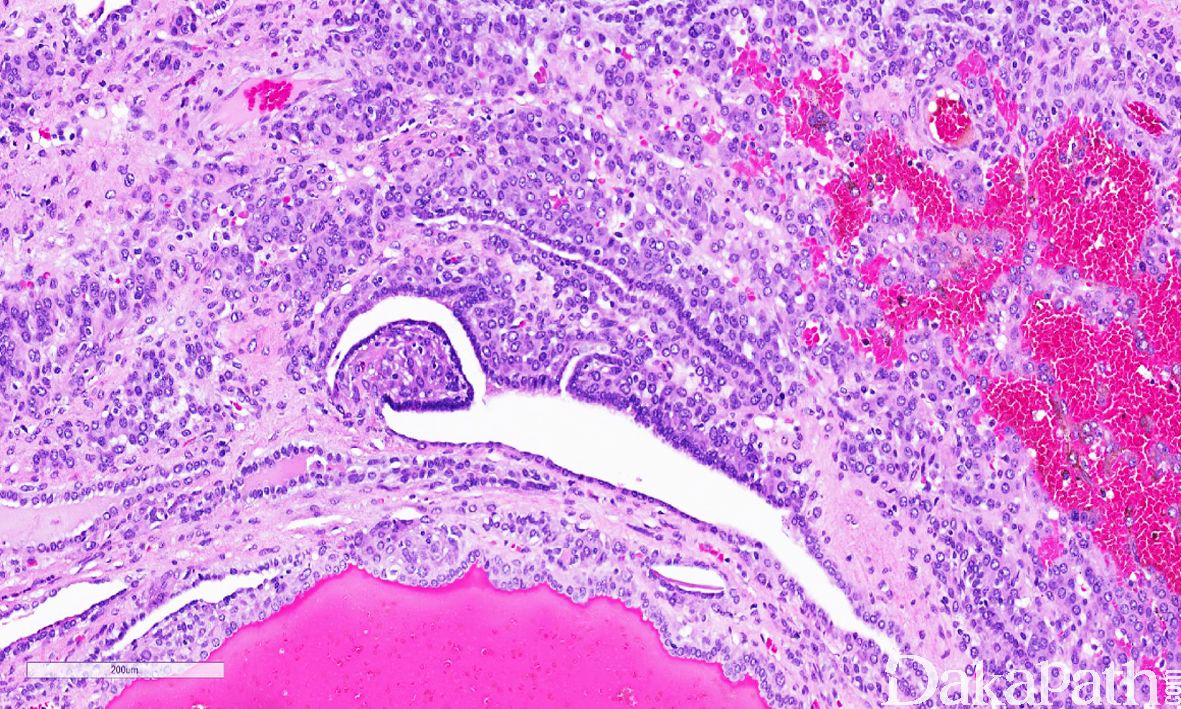

镜下界限清楚,部分带包膜,约半数肿瘤周边可见内陷的良性肾小管。

瘤细胞呈实性片状或围绕分支状血管呈血管外皮瘤样排列,常见间质水肿导致的微囊状结构,肿瘤周边可见瘤细胞围绕内陷的肾小管呈乳头状排列。